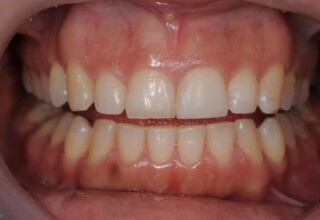

Whitening of non-vital teeth

Teeth with a root canal often lose their brightness and darken to an unesthetic level. Their bleaching requires an excellent root canal and patience. An adhesive filling is placed inside the root to confine the bleaching effect to the tooth part which is visible in the oral cavity. The actual bleaching may require 1-5 short sessions for the placement and renewal of the bleaching material. After the bleaching a high quality adhesive filling is mandatory.

Initial appearance

Final appearance